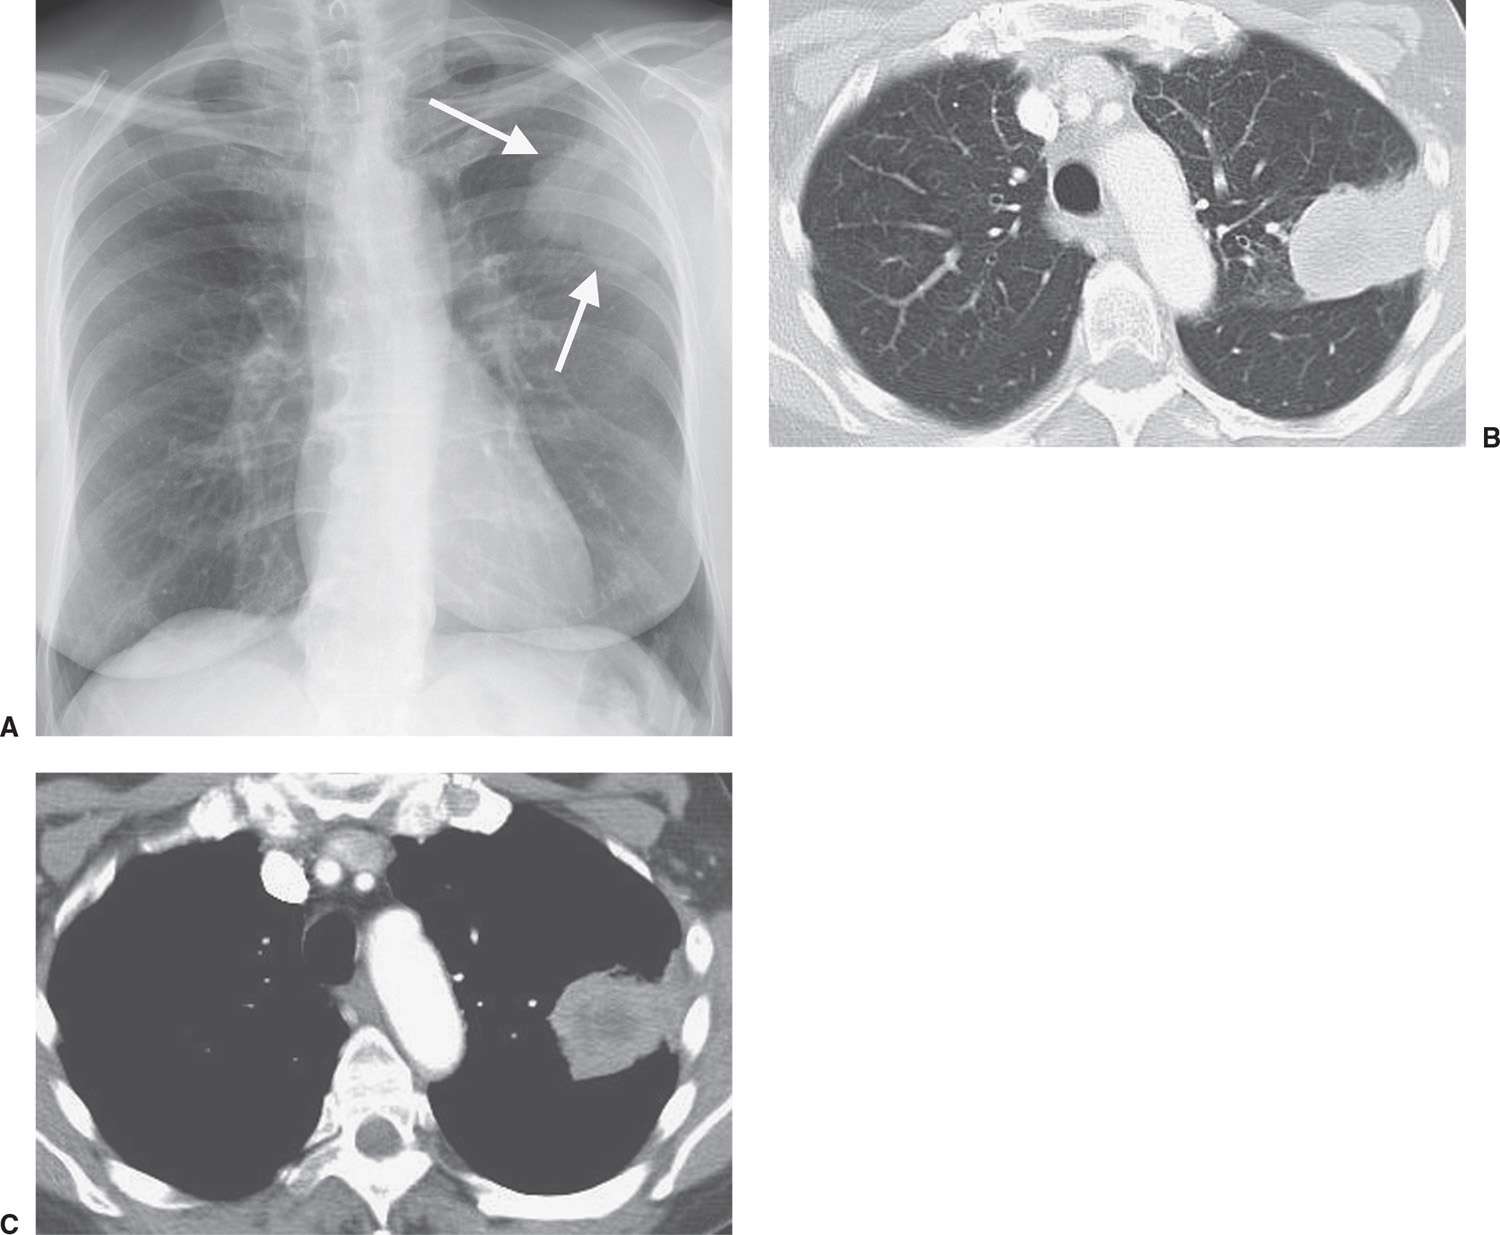

ac Pleural plaques. abTransverse CT image of the chest shows smooth Pleural Plaques Lesion They are indicative of asbestos exposure and typically. This update addresses some of the latest understanding and approaches to management of malignant pleural disease, including use of the rapid multistep scoring system to better predict. Radiological investigation of pleural effusion, thickening, masses, and pneumothorax is key in diagnosing and determining management. Pleural plaques, which are caused by prolonged asbestos exposure,. Pleural Plaques Lesion.

4 Pleural plaques. CT chest (axial view) showing multiple, bilateral Pleural Plaques Lesion Pleural plaques are deposits of hyalinized collagen fibers in the parietal pleura. Radiological investigation of pleural effusion, thickening, masses, and pneumothorax is key in diagnosing and determining management. Abnormalities affecting the pleura—including pneumothorax, pleural effusion, and pleural thickening—can be caused by various. This update addresses some of the latest understanding and approaches to management of malignant pleural disease, including use. Pleural Plaques Lesion.